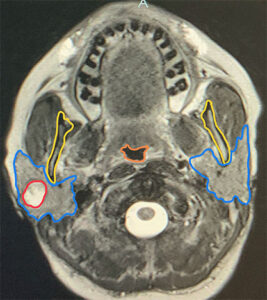

The MRI scan is a very sophisticated scan that shows the parotid gland itself in detail, along with the dimensions and shape of the tumor. It also shows other soft tissue structures such as muscles, fat, blood vessels, lymph nodes, and spinal cord in great detail. It uses magnets to create the image and has no radiation exposure. It is very useful in showing the characteristics of the tumor that may indicate it has features that are suspicious for cancer. And how to best approach tumors that are deeper in the parotid gland for a needle biopsy.

In the images on the right, you can clearly see the anatomy well with both parotids being outlined in blue, the top portion of the jawbone just in front of it in yellow, and the throat outlined in orange. On the top set of images, the tumor is bright white with smooth borders extending from the superficial to the deep aspect of the parotid behind the jawbone, outlined in green. It is impossible from these images to tell if this is a cancer or a benign tumor, but it is clear that the tumor is distinct & not invading the surrounding tissues (bone or muscle).

MRI scan cross section images at the level of both parotids & palate.

The bottom images show a tumor whose borders are not distinct at all; it is hard to tell where it begins or ends; a rough outline is drawn in red but there is the possibility that the tumor is invading the muscles behind it. This lack of clear borders very much indicates a cancerous process. The areas of the lymph nodes in the neck can also be seen to see if there are any enlarged suspicious lymph nodes. This allows the surgeon plan the optimal surgery, and what type of reconstruction should be done.

The MRI scan showed a solid mass with distinct borders in the superficial aspect of the parotid gland, and no enlarged lymph nodes in the parotid or the neck. On MR, both parotids are outlined in blue, the top portion of the jawbone just in front of it in yellow, and the thyroid is outlined in orange. The tumor (cancer) is outlined in red. The FNA (needle biopsy) indicated that it was a low-grade carcinoma, favoring acinic cell carcinoma. An ultrasound was performed the day before surgery in the office by Dr. Larian, which showed the exact dimensions & location of the tumor, as well as looking at the lymph nodes in the neck; again, fortunately, the lymph nodes appeared all to be normal.

The MRI scan of a solid mass with distinct borders in the superficial aspect of the parotid gland, and no enlarged lymph nodes in the parotid or the neck.

MRI shows a mass in the superficial parotid (outlined in Red).